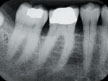

Digital X-Ray

Our office is equiped with Digital X-ray .

Dental digital radiography has been shown to be every bit as diagnostic.